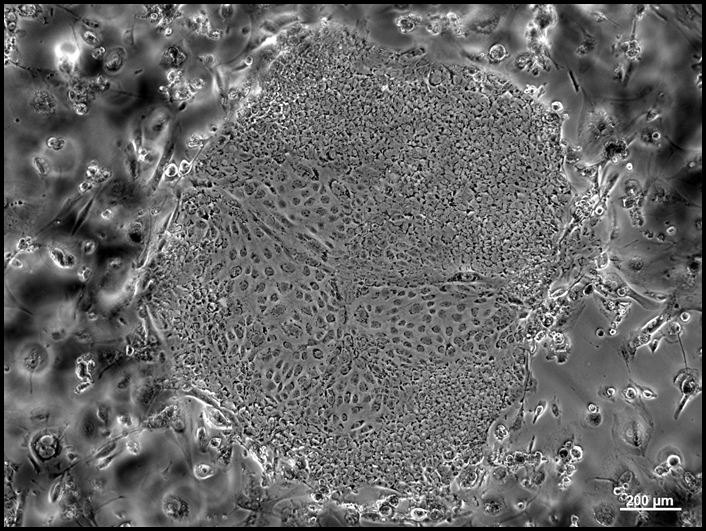

mini-BIOMAN 2016: Stem Cell Production in a Regulated Environment

Rapid advances in stem cell and organ regeneration have put the biomanufacturing industry in a position of eminent uses. Stem cells therapies such as the treatment of macular degeneration are already in use and many more potential applications are currently in clinical trials at all phases. Lab grown organs, such as bladders, have been implanted in humans and advances in regeneration of other organ types are in development and animal trials today. The expansion of these products into human use has led to the need for training and skills in the application of stem cell technologies in an FDA regulated, current good manufacturing practice (cGMP) environment.

This workshop will introduce participants to the theory, concepts and practices of stem cell and organ regeneration in a cGMP environment. Workshop participants will conduct clean room gowning and advanced hands-on activities including the maintenance, transfer and differentiation of stem cells, and analytical methods to determine the success of directed differentiation. Additionally, guest lectures from industry experts and a tour of the Wake Forest Institute for Regenerative Medicine in Winston-Salem, NC will be included. Following the workshop, participants will be able to:

6.    Aseptically feed, transfer and treat stem cells for differentiation.